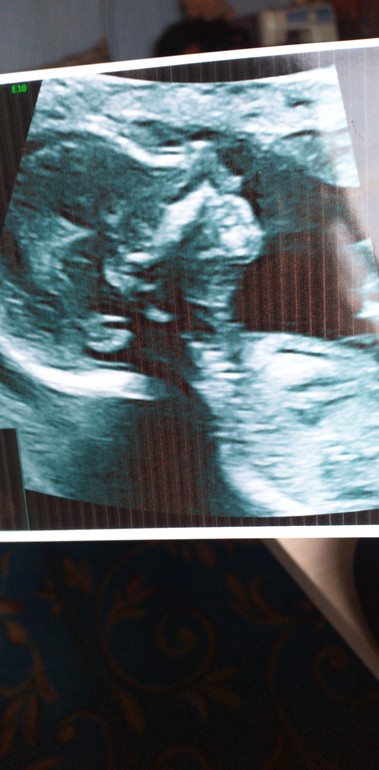

УЗИ 16-17 недель. Третий малыш.

С крошкой по узи все хорошо. Весим 162 грамма примерно, все в норме, мозг без патологий, брюшная полость без патологий, лицо без патологий, сердце без патологий.

У нас будет девочка) Я не верю. Не укладывается в голове... Такое бывало, но только не со мной! Дочка!!